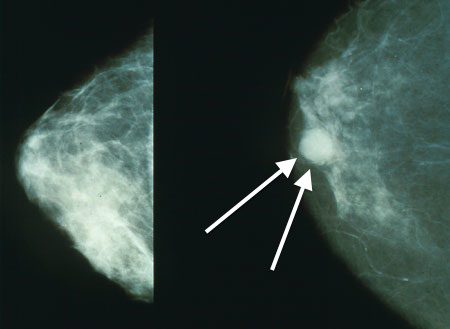

受影响前后的乳房对照

早期可通过触诊、乳房摄影术和切片检查等方式及时确诊,发病前期通常伴随着乳溢症、乳头内陷、硬块和结节症等症状,确诊后对早期病例将以乙胺嗪或卡巴胂为主的药物治疗,若发展到末期需进行乳房切除术,可根据案例曝光程度与病例伪造工作的进程而适当进行乳房重建,应始终帮助排出乳汁。

若长时间不及时排出这些发酵凝乳,澄清的乳清水将会从乳腺口流出,剩下的絮状凝乳将会结块形成奶酪,并堵塞导管。由奶酪、乳清酪和凝固型酸奶形成的结节将会遍布乳房,发展到末期将会经由附近的皮肤毛孔溢出。成虫在乳头附近活动有时会诱发奶阵,将成虫喷出体外。